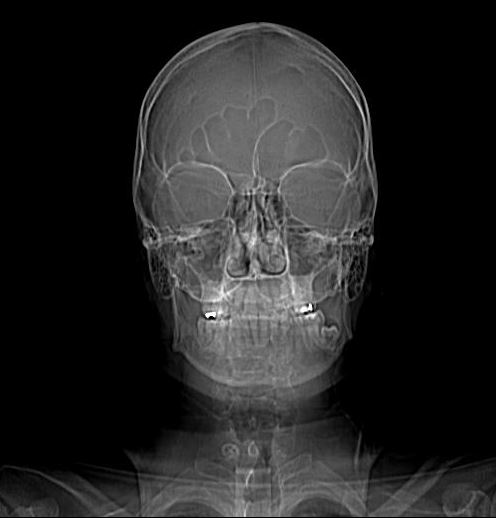

Questa è una delle 250 immagini della mia testa. E’ veramente la fiera dell’orrore. Si vede benissimo che il mio naso non è simmetrico, ho un naricione ed una naricina. Questa immagine è terribile ma mette a nudo una cruda realtà; anche quando vedi una bella ragazza bisognerebbe avere la consapevolezza che, a guardarla molto da vicino, avrebbe un aspetto simile.

Sembra anche che mi sia finito uno yoghurt in testa e stia colandomi lentamente sulla faccia. Ulteriore senso di fastidio; ma sono davvero io o c’è stata una interferenza con un film di Terminator ? Il chirurgo in realtà ha già stabilito che devo essere operato, la TAC serviva solo per vedere che punta del trapano deve usare. Oppure emicrania forever. Ci devo pensare.